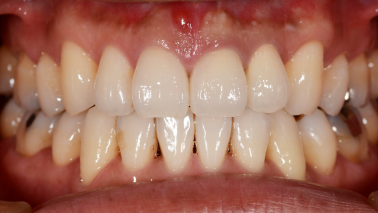

下の口腔内写真は初診時と矯正治療+補綴治療後のものになります。

一般的な矯正歯科ではできない審美治療など、矯正後のその先まで考えて治療計画を立案し治療を行っていくことが出来ます。

連結してあった前歯の被せ物(歯茎まで黒くなっている)も矯正後にきれいに治療することが出来ています。

歯並びが悪いと見た目が悪いだけではなく歯磨きがしづらく、噛み合わせが悪いことで力のかかり方が不均一になってしまい歯に亀裂が入り虫歯になりやすくもなります。

1本1本の歯にはそれぞれ役割があり、矯正治療を行うことでそれぞれの歯に適正な咬合力がいき渡るようにすることが出来、虫歯や歯周病になりづらい口腔内に、さらに審美的にもなります。